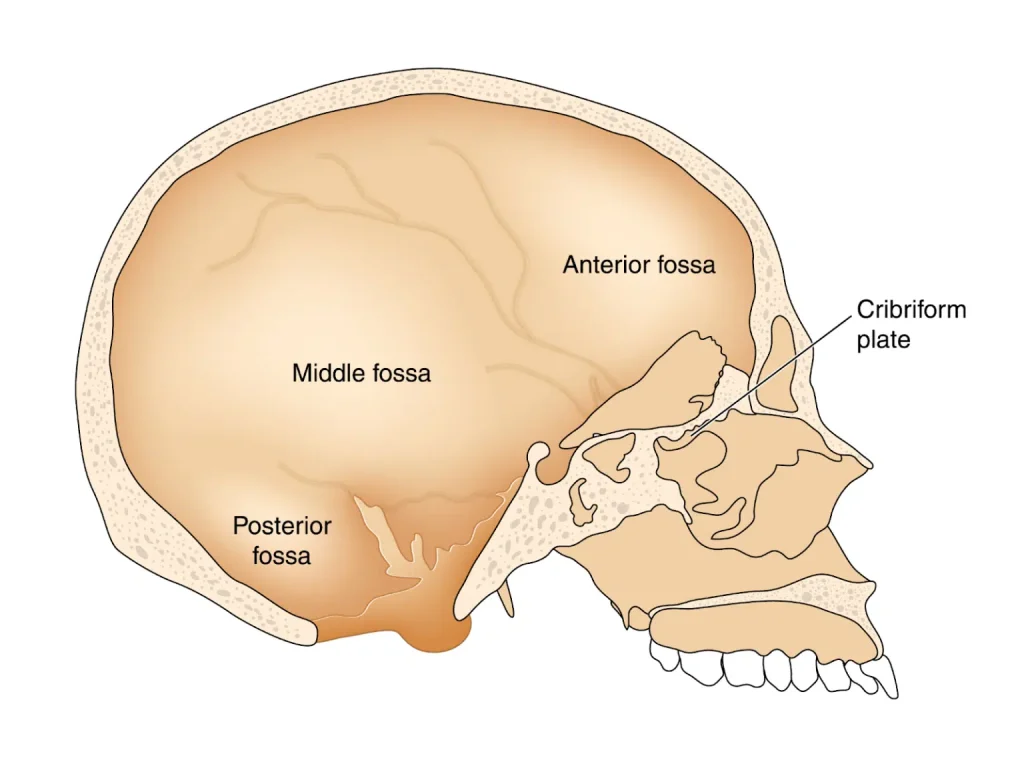

Hố sau là vùng phía sau hộp sọ, chứa:

- Hai bán cầu tiểu não

- Thùy nhộng

- Thân não

- Não thất IV